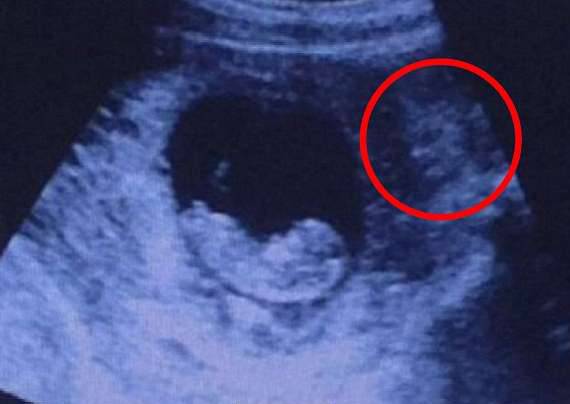

这张照片被上传到网路后,引发了一场大讨论。有些网友认为这个模糊的影子像恶魔,它正在注视胎儿,看起来很恐怖。也有人认为这是印度教的神,更有人认为它是友善的人鱼。

▼右侧的阴影处有明显的人形。